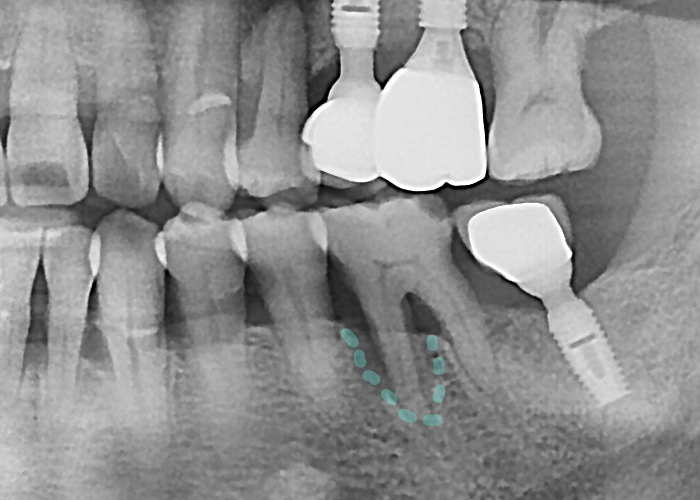

하루임플치과

PDRN주사 + 골이식 시행

다행히 최근에는 뼈가 부족해도

여러 가지 보완 방법이 있습니다.

대표적인 것이 골이식술입니다.

이식재를 이용해

부족한 뼈를 보강해 주고,

시간이 지나면서 이식된 뼈가

환자의 뼈와 융합되어

새로운 기반을 만들어 줍니다.

전과는 다르게 엑스레이 사진상에서

뼈가 차오른 모습입니다 ^^